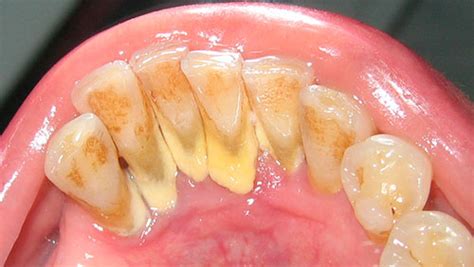

Acumulación de sarro dental en los dientes.

El sarro, también conocido como “cálculo dental” u “odontolito”, es una sustancia mineralizada y dura que se acumula sobre los dientes cuando no se elimina la placa bacteriana. Colegiado nº 28007842, odontóloga experta en tratamientos ortodónticos desde 2005, explica que el sarro aparece tanto por fuera como por dentro de la línea de las encías, y su posición puede afectar en su color.

El color del sarro depende de la edad y de dónde aparece en la boca. El sarro se distingue por su color, que puede ir de blanquecino a pardo.

- Sarro supragingival: El sarro sobre la línea de las encías, también denominado cálculo supragingival, es amarillo o tostado.

- Sarro subgingival: El cálculo subgingival es el sarro que aparece debajo de la línea de las encías, el cual puede ser marrón, negro o verde.

El sarro puede ser de color amarillento, marrón o verdoso en casos más severos. El sarro negro se compone de las mismas sustancias que las variantes más claras, pero incluye otros materiales procedentes de los fluidos circundantes.